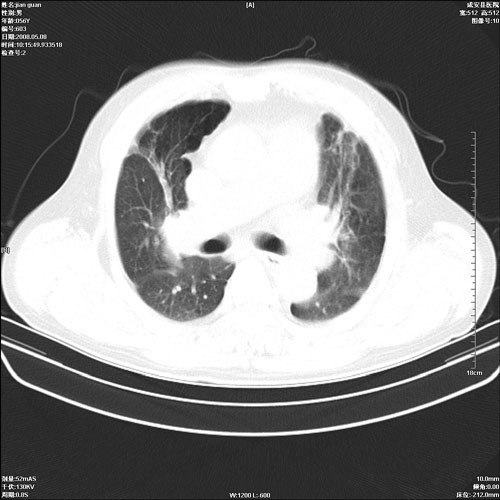

病人 男 60岁 主诉 胸闷 无明显发热 一般情况尚可。

肺结核?

两上肺陈旧性结核;慢支肺气肿、伴感染?

1.右上肺陈旧性肺结核.

两上肺陈旧性结核;慢支肺气肿

1.两上肺陈旧性结核;慢支肺气肿。

陈旧性肺结核

考虑.两上肺陈旧性结核;慢支肺气肿。肺心病

两上肺陈旧性结核,慢支肺气肿。

两上肺陈旧性结核;慢支肺气肿。肺肺间质纤维化

两上肺陈旧性结核;慢支肺气肿。

1.陈旧肺结核;

2.慢支肺气肿;